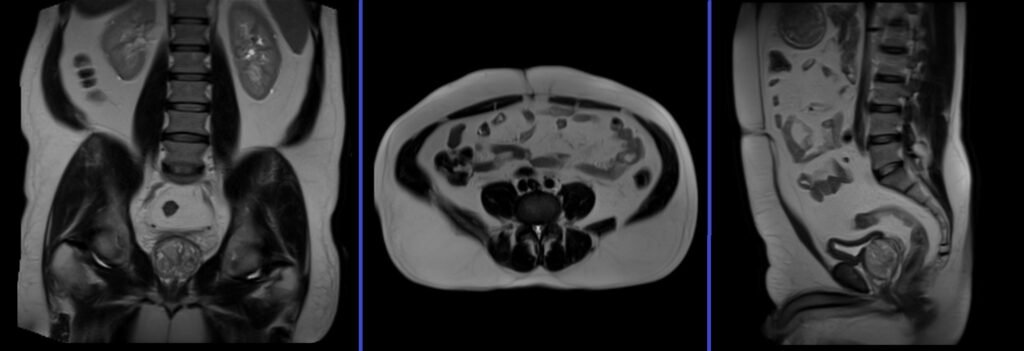

Lumbosacral Plexus MRI Localizer

A three-plane localizer must be taken at the beginning to localize and plan the sequences. Localizers are normally less than 25 seconds and are T1\T2-weighted low-resolution scans.